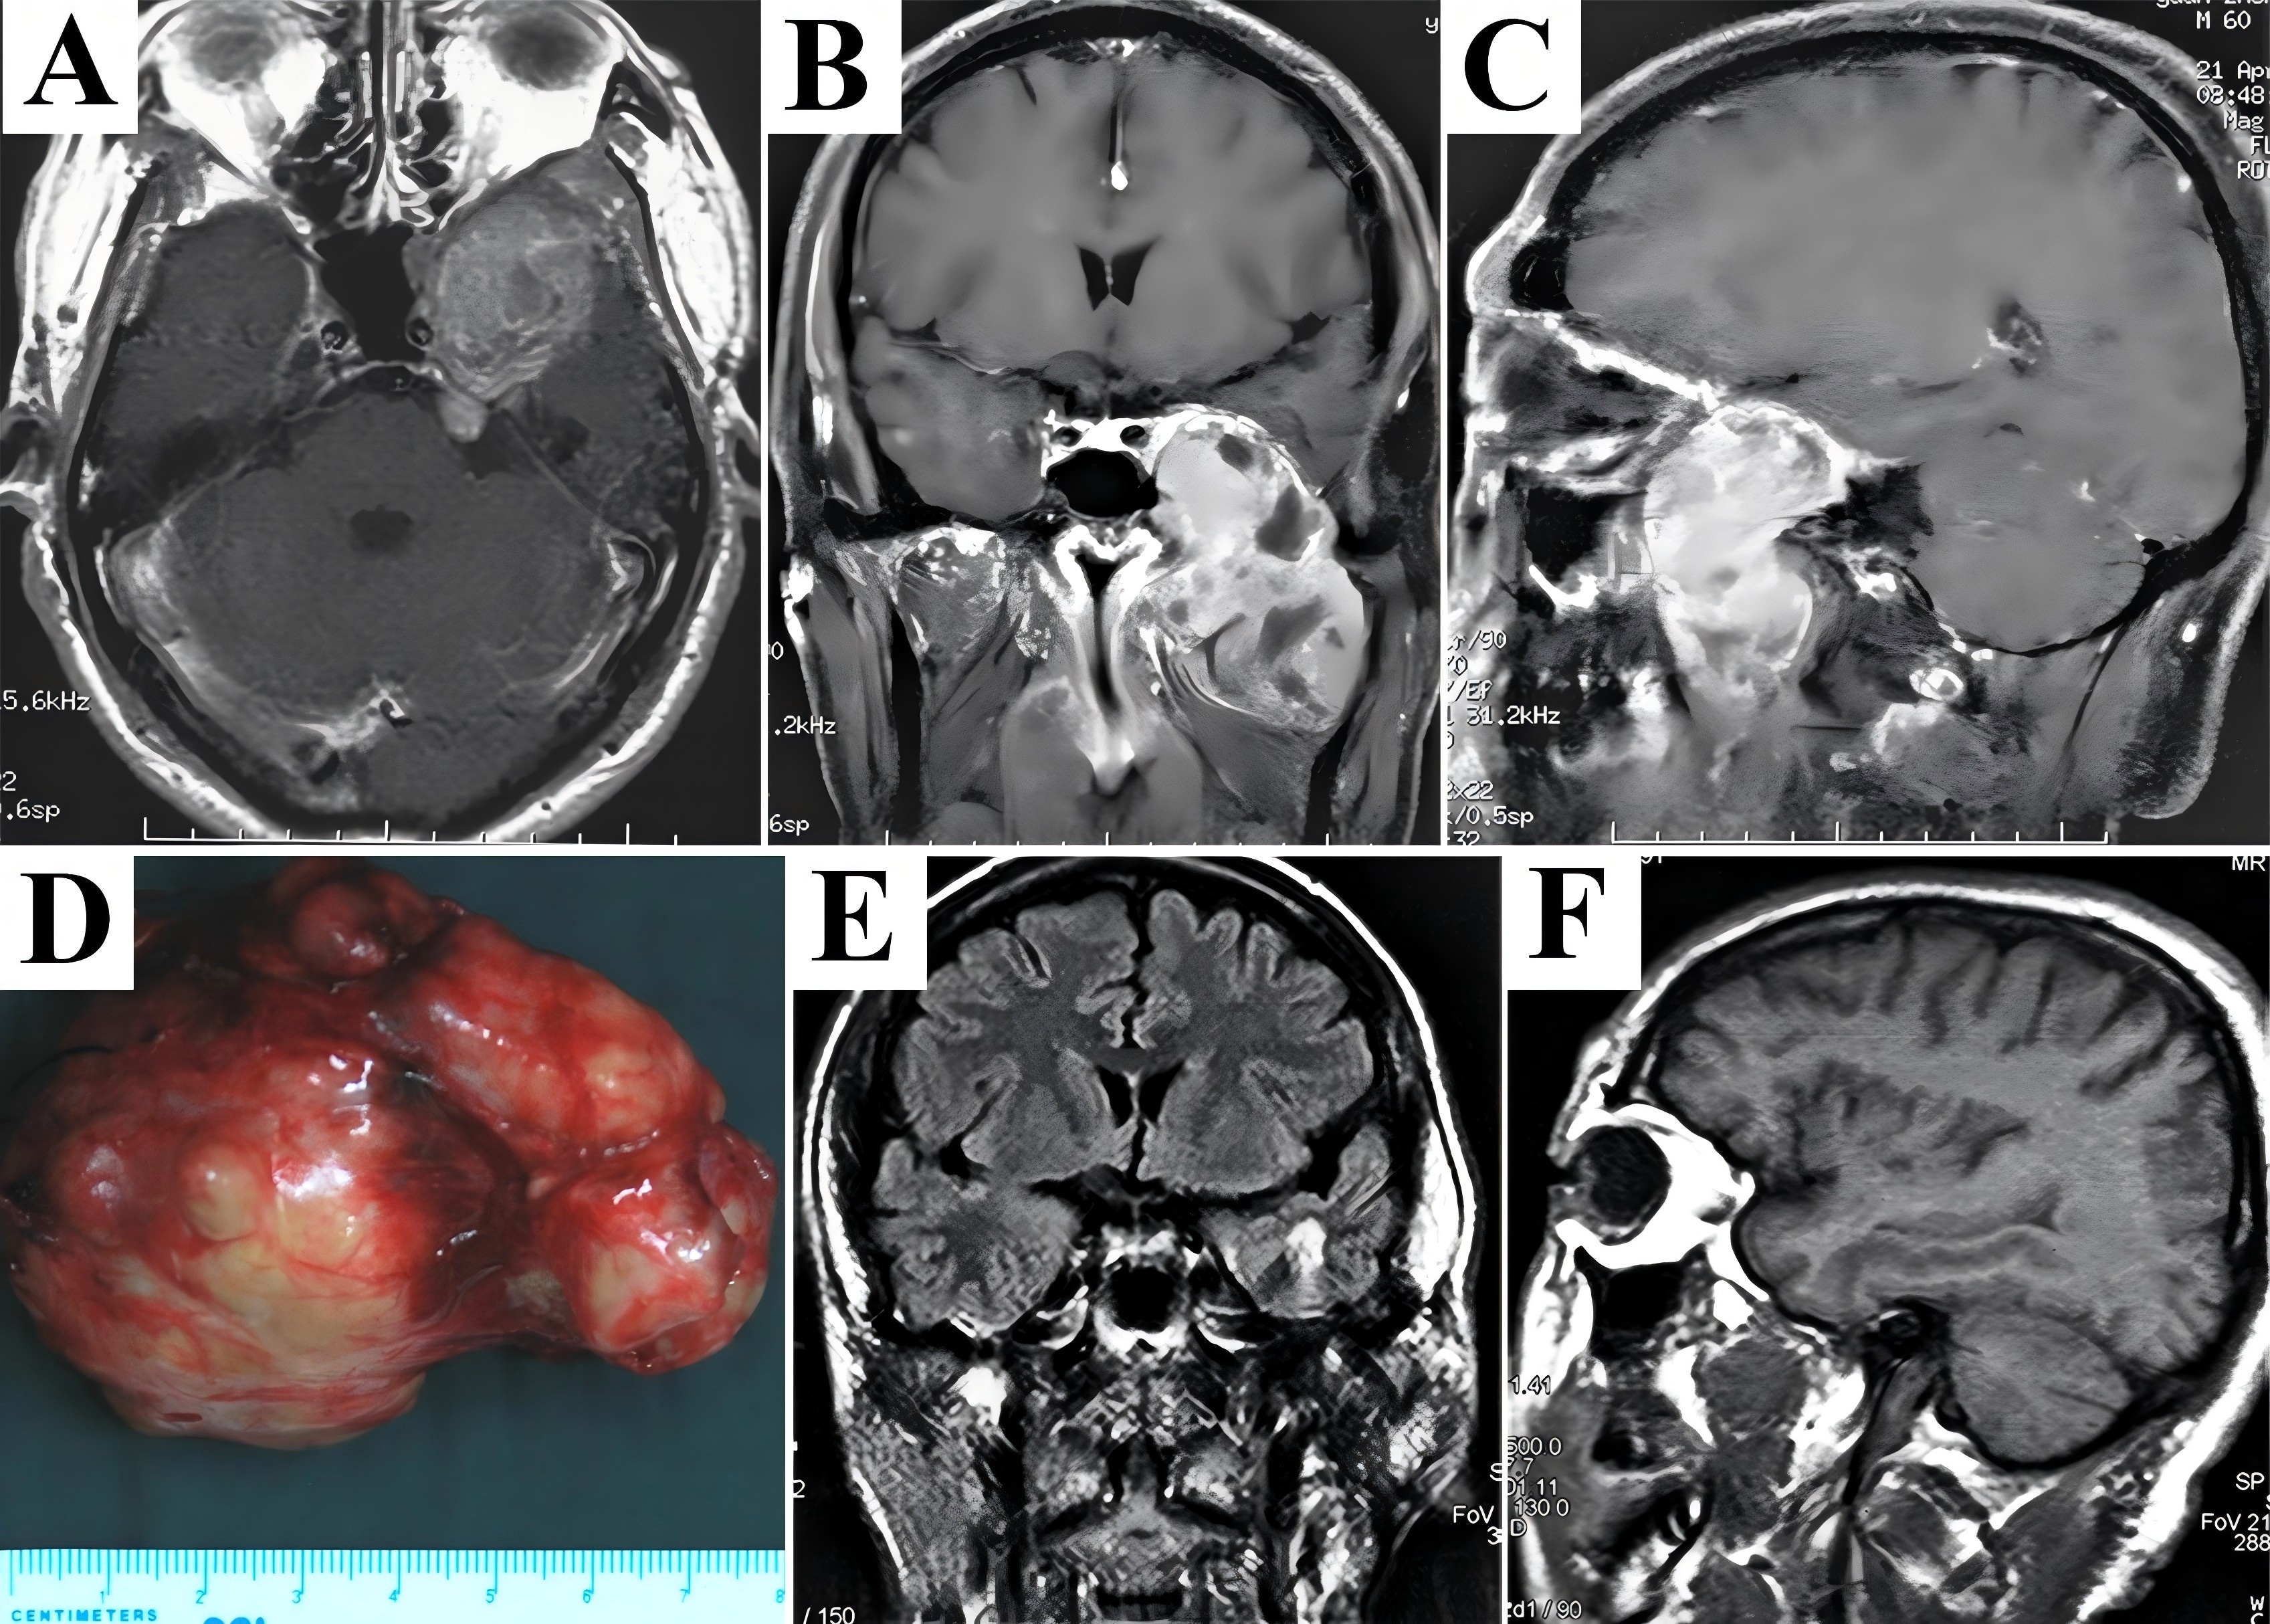

A 32-year-old man tolerated nasal obstruction, anosmia, and persistent facial numbness for 4 months, and sought medical attention when facial deformity was developed. Flattening of the left nasolabial fold and slightly mouth drooping were observed on admission. Preoperative CT scans showed a huge lesion centered at the left petroclival region destructing the petrous bone and occupying multiple craniofacial compartments (Fig. 2A). Significant enhancement of the extensive mass abutting the mandible and migrating into the subdural region on MRI (Fig. 2B-D) presented great challenges since sufficient exposure and complete resection in one-stage without severe bleeding could not be achieved solely from any approach. Therefore, the maxillary swing approach combined with the Kawase’s approach were performed. After reflection of the maxilla laterally, the lesion was exposed and feeding arteries (probably the internal maxillary artery) were ligated and transected. The extracranial portion of the rubber-like multilobulated tumor was transected at its extension into the Meckel’s cave using a scalpel because of fibrous consistency. Dissection continued through the petroclival region to the cerebellopontine angle (CPA) using the Kawase’s approach, and remnant subdural segment was completely stripped away from the arachnoid membrane, allowing resolution of the mass effect on the brainstem. Following hemostasis and antibiotic irrigation of surgical field, multilayer reconstruction of skull base started with dura suture. Then the extradural area was packed with the temporalis fascia, periosteum, and pedicled temporalis muscle to reinforce dural repair. CT scans immediately after surgery demonstrated complete resection (Fig. 2E). The patient developed facial numbness and suffered temporary dry eye postoperatively. Intracranial infection secondary to cerebrospinal fluid (CSF) leak occurred 4 days after surgery, and was resolved by antibiotic therapy accompanied by lumbar drain. The final diagnosis based on histological findings was schwannoma. During follow-up period of 49 months, there was no evidence of recurrence (Fig. 2F-H).

Figure 2. A combined craniofacial resection of the giant and rubbery schwannoma was performed. Preoperative CT scans revealed an extensive lesion destructed the petrous bone and migrated both anteriorly and posteriorly (A). Significant enhancement mixed with discrete hypointensity on contrast T1-weighted MRI in axial (B), coronal (C), and sagittal (D) planes probably demonstrated a hypervascularized lesion with features of fibrosis. After removal of the extracranial portion via maxillary swing approach, dissection proceeded along the intradural segment through the Kawase’s approach to obtain a complete resection in one-stage, which was shown on CT scans immediately after surgery (E). Postoperative MRI detected no tumor recurrence during the follow-up period (F-H). CT, computed tomography; MRI, magnetic resonance imaging.